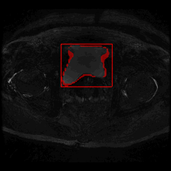

这是我在学校期间参加的一个比赛项目,项目的问题是在医学图像中准确提取膀胱边界以及对肿瘤块的识别。数据集由中国计算机大赛人工智能挑战赛提供。下图是数据集的案例,左图为原始医学图像,右图是人类医学图像专家所做的标注:

除了模型外的工作,我们还对图像数据进行了预处理,以及利用数字图像处理的一些方法进行结果提升,但这些工作由于篇幅原因省略。我讲我们模型输出结果制作了动图,具体如下,其中左边为我们挑选肿瘤面积较大的样本,右图为膀胱壁较清晰的样本,红色为膀胱壁而青色为膀胱肿瘤。